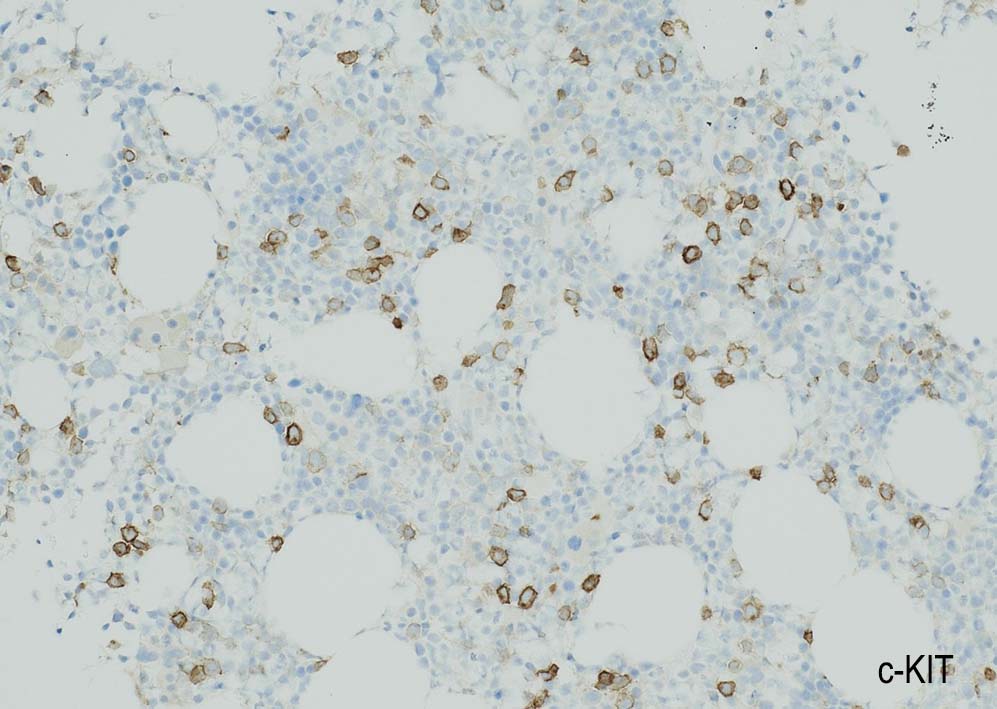

Megakaryopoiesis; Mgkは増加している. 多数の分離円形核巨核球が出現している. microMgkが増加している.